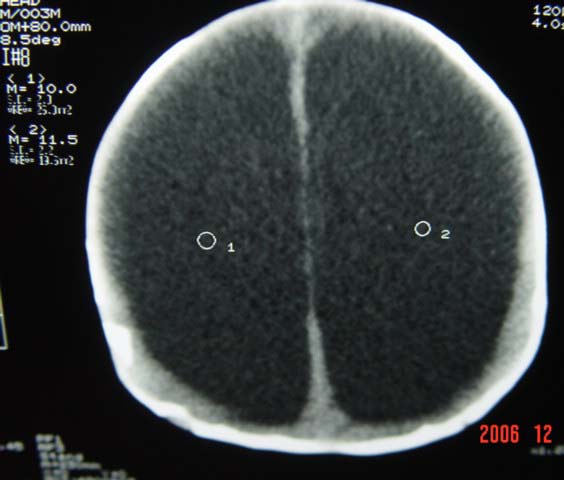

3m,出生时有新生儿吸入性肺炎、hie、化脓性脑膜炎,近一个月发现头围增大(51cm),无恶心呕吐。

3m,出生时有新生儿吸入性肺炎、hie、化脓性脑膜炎,近一个月发现头围增大(51cm),无恶心呕吐,脑室系统全程扩张,脑皮质变薄,结合病史考虑交通性脑积水

3m,出生时有新生儿吸入性肺炎、hie、化脓性脑膜炎,近一个月发现头围增大(51cm),无恶心呕吐,脑室系统全程扩张,脑皮质变薄,结合病史考虑重度交通性脑积水。